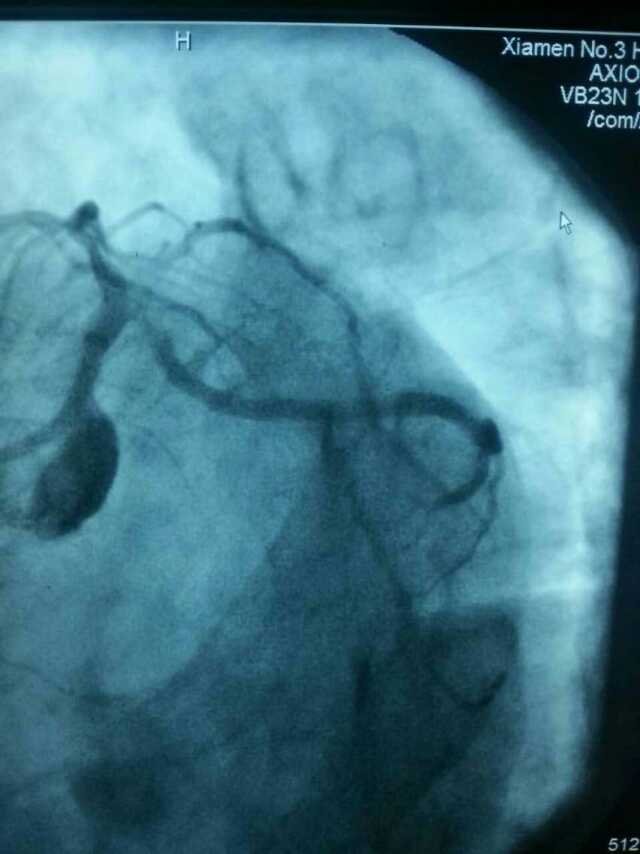

3月20日,家住翔安的庄先生为感谢伦理片 心血管内科的医护人员在第一时间对他的病情给予明确诊断,并及时采取有效治疗措施,让他的心脏病很快得到康复回家。特地送来一面写着“德医双馨,妙手回春”锦旗以表达他们满满的感激之情。